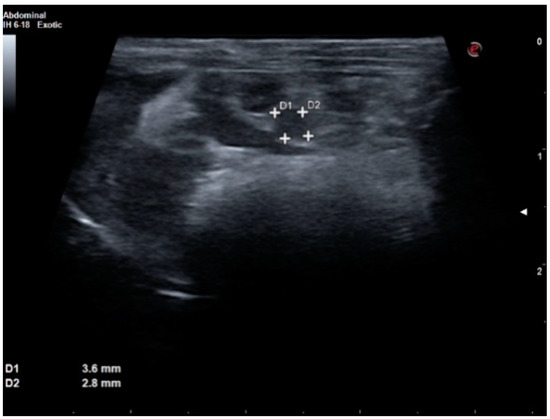

2. Case Report